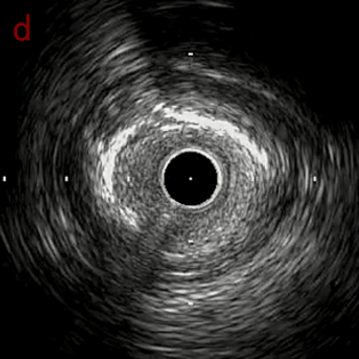

IVUS imaging

IVUSでは8時方向からPD枝がはいいてくる。

OAS low speedによる引きのsandingを3回行いIVUSを確認するとa-cでは心筋側側へのOASによる良好なbias変化と、それに伴いdの健常側への危険なbias変化を認めた。

そのためcでIVUSマーキングを行い、その点より引きで赤線のpinpoint OAS high speedを行い、dに関してはinjury回避のためにOASを当てない方針とした。

それに伴いdではbiasがさらにtentingのIVUS所見にへんかしhigh injury riskと思われた。

引き続き造影で確認してpinpointで引きのOAS high speedを3回さらに追加のためcでIVUSマーキングを行い、その点より引きで赤線のpinpoint OAS high speedを行い、dに関してはinjury回避のためにOASを当てない方針とした。

High riskのbias所見へと変わっていったdの部位に関してはpinpoint OASを行うことでinjuryなく治療できた。

OASを行うたびに徐々に心筋側側にwire bias変化をきたし、石灰化病変部に関してはそれが良い変化となっているが、distal reference (d) に関してはinjury riskの高いbias変化となっていった。

本症例は石灰化病変部に関してはsandingを行うことで石灰化内に食い込み、良好なbias変化をきたした。しかし、その一方でwire biasが心筋側側にかかることでdistal referenceで健常側への危険なbias変化をきたした。

OASの後、繰り返しIVUSを行うことでwire bias変化を捉えることができる。またIVUSマーキングすることで、ピンポイントに削りたいところだけを安全に削ることができる。